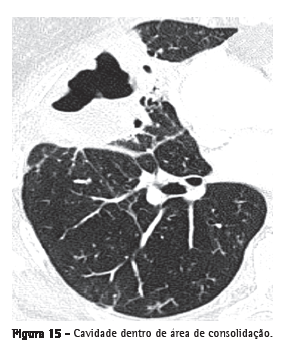

Cavidade (escavação)Representa espaço que contém gás, com ou sem nível líquido, dentro de um nódulo, massa ou consolidação pulmonar. Geralmente ocorre pela eliminação ou pela drenagem da parte necrótica pela via aérea (Figura 15) ou para o espaço pleural. As paredes costumam ter contornos irregulares e medir mais de 1 mm de espessura. "Cavidade" não é sinônimo de "abscesso". O termo "cavitação" não deve ser usado como sinônimo de "escavação": na língua portuguesa, "cavitação" tem significado diferente, e seu uso é incorreto.(7)